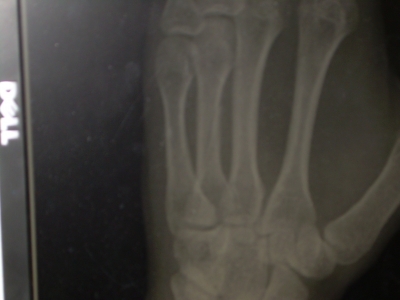

3. The potential image manipulation when dealing with X-rays is AWESOME to any gadget appreciator. You can zoom in, play with contrast... really if it hadn't been my own bones I'd been looking at I would have found it entirely fun.

Ooo! Can you get hold of the xrays next time you visit the doctor? Or snap a picture of them?